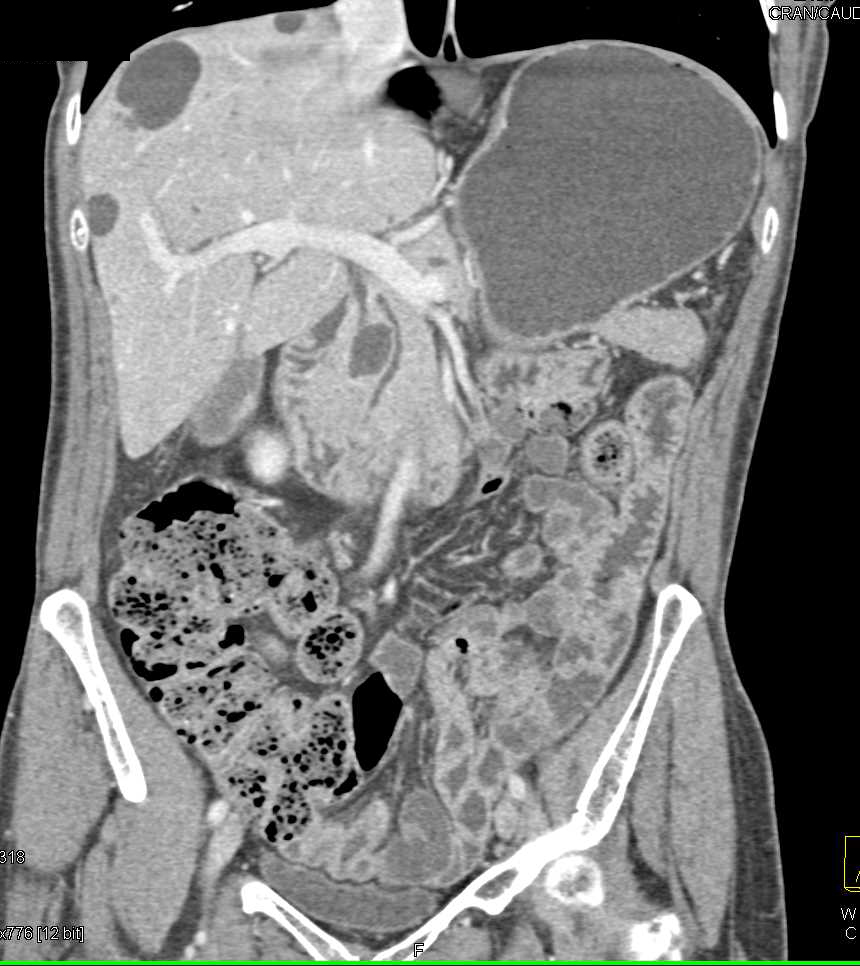

Cystic Neuroendocrine Tumor in the Uncinate Process